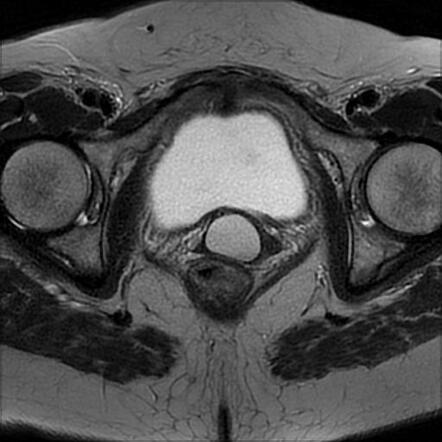

هیستروسالپنگوگرافی (HSG) یک آزمایش تشخیصی است که به ما امکان میدهد عملکرد لولههای رحمی را ارزیابی کنیم.